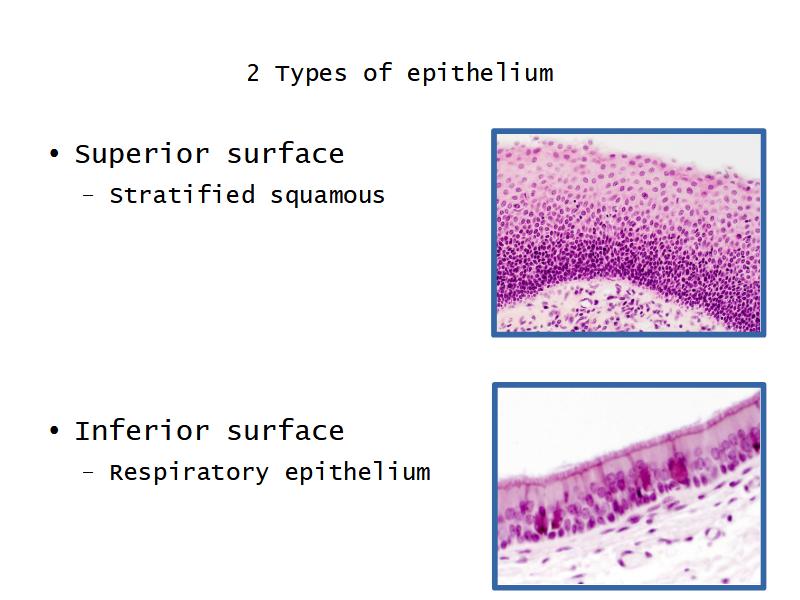

- Slide 111: Epiglottis

Epiglottis

Respiratory epithelium

- Pseudostratified

- Ciliated

- Columnar

- Epithelium with

- 4 Cells

- Ciliated columnar cells

- Non-ciliated columnar cells

- Goblet cells

- Basal cells